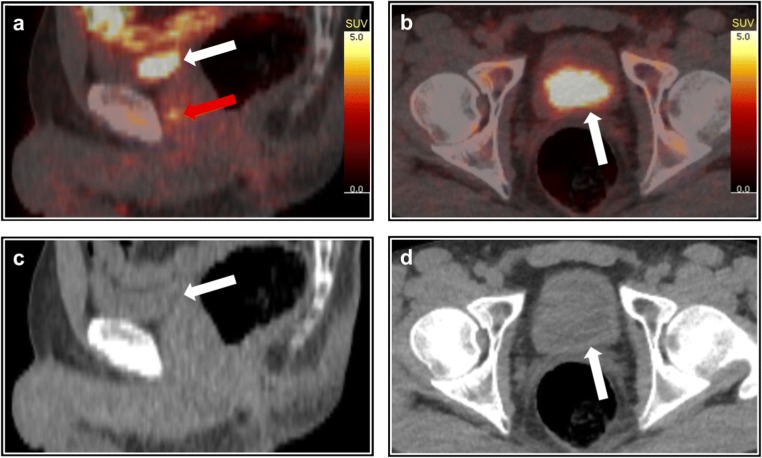

Fig. 1.

Positron emission tomography (PET) with 82Rubidium is widely used for clinical quantification of myocardial blood flow [1]. Increased 82Rb uptake has been reported in breast cancer [2], lung cancer, lymphoma, multiple myeloma [3], metastatic renal cell carcinoma [4], and malignant pheochromocytoma [5]. Recently, we validated 82Rubidium PET/computed tomography (CT) for tumor blood flow measurement in prostate cancer [6, 7]. We have found that around 90% of patients had low urinary 82Rubidium activity. However, in thirteen out of 127 patients, we observed very high 82Rubidium activity in the urinary bladder, shown with white arrows on fused PET/CT images (a, b), and corresponding low-dose CT (c, d). The red arrow marks the prostate tumor with increased 82Rubidium uptake (a). Rubidium is a potassium analogue [8, 9], and therefore, rubidium has frequently been used as a marker of potassium in transport studies [10, 11]. It has been shown that renal excretion of 86Rubidium and potassium is parallel [8] and that renal 86Rubidium excretion can be accelerated by acetazolamide, which increases potassium excretion [8]. The increased potassium/rubidium excretion was explained in six patients as one patient had severe hypokalemia, one had mild hypokalemia, and four patients received thiazides, which is also known to increase renal potassium excretion. The remaining seven patients had normal plasma potassium and their medical records revealed no explanation for the suggested increased renal potassium excretion. To our knowledge, enhanced renal potassium excretion has not previously been visualized on 82Rubidium PET/CT. This finding may also be of relevance for the ongoing research on renal blood flow measurement with 82Rubidium PET/CT [12]. Increased renal rubidium excretion reduces the arterial rubidium concentration by a few percent at most and does not affect myocardial uptake